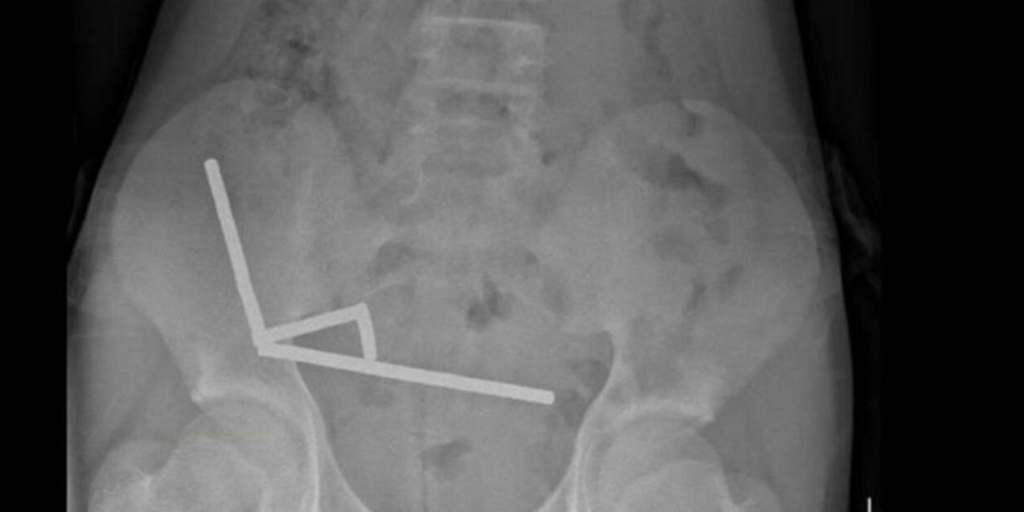

I medici hanno effettuato una radiografia, che ha mostrato una lunga catena di dischetti magnetici formata nello stomaco e nell’intestino del ragazzino. Gli oggetti si erano uniti tra loro, schiacciando i tessuti intestinali da punti opposti.

A quel punto è stato necessario un delicatissimo intervento chirurgico, durante il quale è stata asportata parte dell’intestino, per evitare danni irreversibili e prevenire gravi infezioni. L’operazione è riuscita, ma il rischio corso è stato elevato. Il paziente è rimasto in ospedale per otto giorni, prima di essere dimesso.